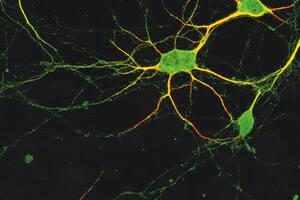

Neurofisiologia

Efeitos da aversão

Situação que causa repulsa aumenta atenção e percepção visual

Por Ricardo Zorzetto